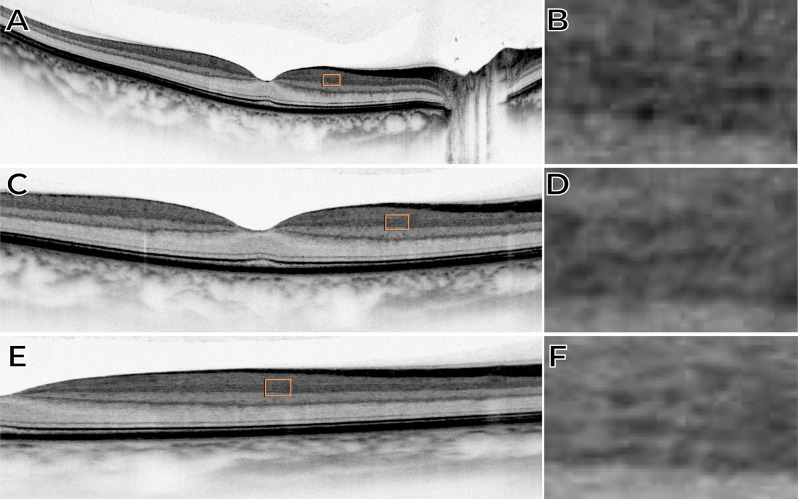

Methods: This retrospective, cross-sectional image analysis study included three healthy individuals who underwent macular OCT imaging. Two subjects were imaged with SD-OCT devices (Nidek RS3000 Advance and Zeiss Cirrus 6000), while one subject was imaged with a swept-source OCT (SS-OCT) device (Topcon Triton DRI). High-density B-scans (1024 A-scans per B-scan) with 120 repetitions for noise reduction were analyzed in both standard and inverted grayscale display modes. The impact of scan size (12 mm, 6 mm, and 3 mm) on IPL visualization was also evaluated.

Results: In conventional grayscale, IPL stratification was indistinct. However, inverted grayscale revealed five IPL sub-bands in all cases, particularly in the parafoveal region where the IPL is thicker. Hyperreflective dots near IPL-1, likely representing the superficial capillary plexus, were also identified. The 3-mm scan protocol provided superior sub-layer differentiation compared to 12-mm scans. However, SS-OCT images did not allow for the distinction of the five IPL strata.